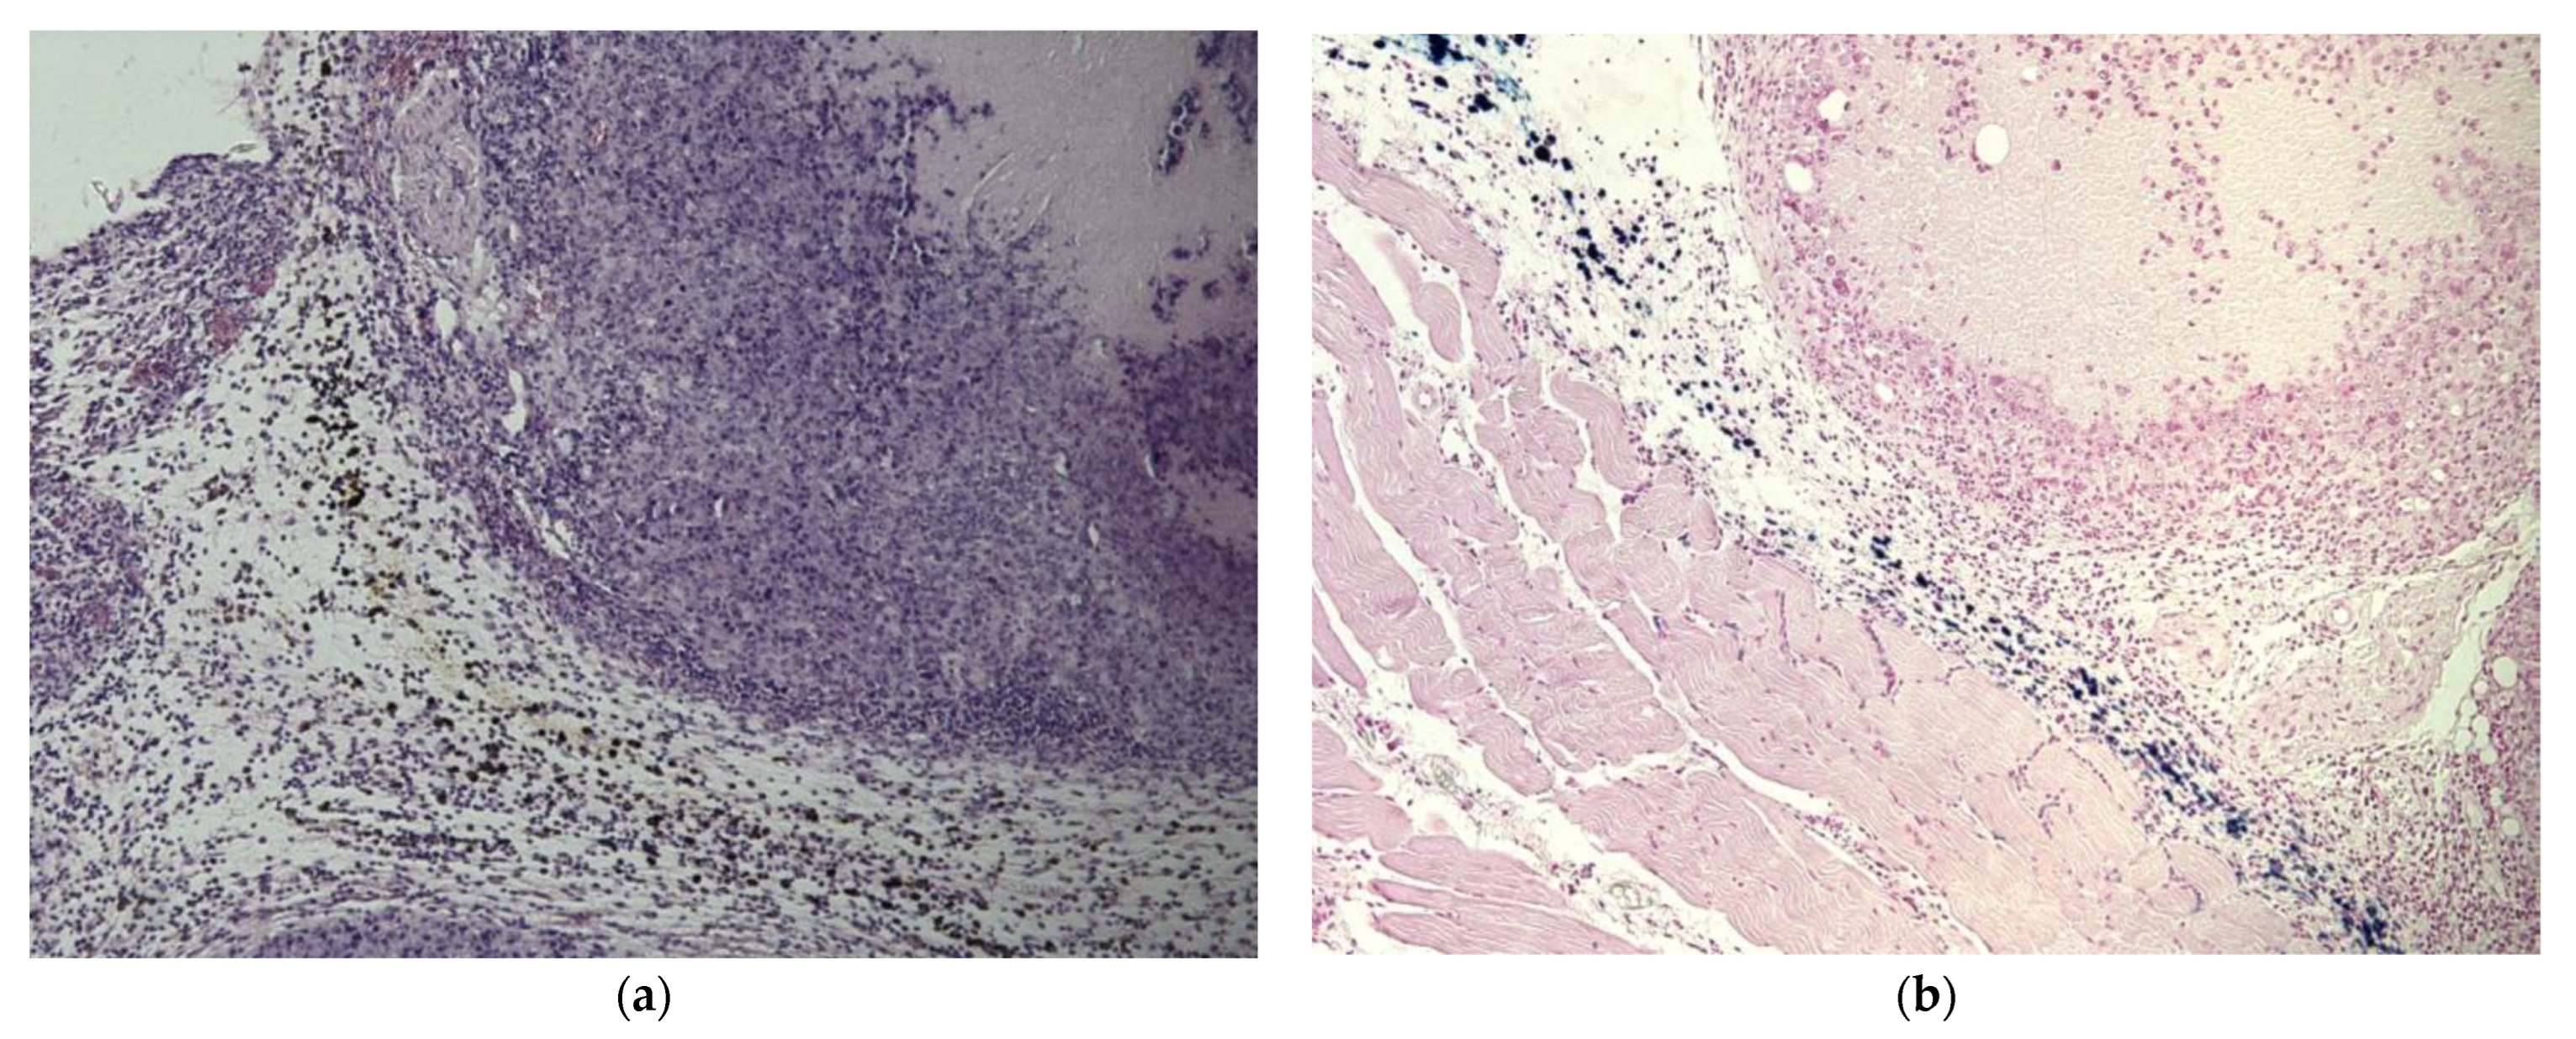

3.2.3. Group III: EcPHL-Untreated Mice Administered with mNP via Local Intratumor Injection

3.2.4. Group IV: EcPHL- and mNP-Treated Mice

- EcPHL improves mNP distributions and the spread radius in the tumor tissue from the local inoculation point in comparison to mice tumor tissue without immunomodulation. The mNP were observed in the necrotic areas and fatty and connective tissues, as well as in the TAMs, both intra- and extracellularly. Intracellular iron-containing exogenous pigments were visible in the cytoplasmic granule. A large number of mNP were observed in inflammatory infiltrates, necrotic areas, and macrophages.